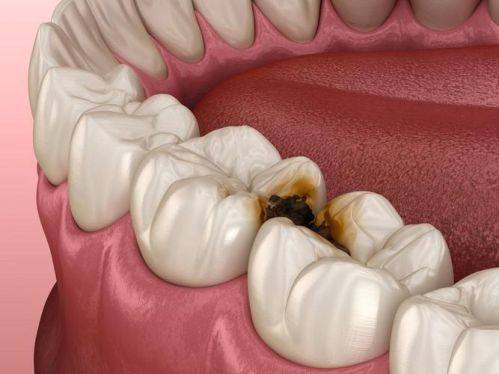

牙体牙髓病诊疗:针对龋病、牙髓炎等常见牙体牙髓问题,可精细诊断并开展规范治疗,有效缓解患者牙痛等不适症状。